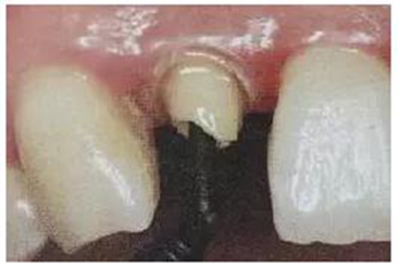

6. 纖維樁的試放和裁戴

纖維樁試放時應用鑷子夾持將其插入預備的根管樁道中(這涉及無菌觀念和操作),就位時無阻力可稍有錮住感。

(鑷子夾持(正確))

(污染手套夾持(錯誤))

(技工鉗裁剪(錯誤))

試放后應按所需長度用細粒金剛砂車針切割裁剪。

(粘樁堆核固化后裁剪)

為防止裁剪過程中有可能造成樁表面的污染,可以粘結固位后再進行裁剪。

操作時。光固化燈應在樹脂核成形后,頰、舌、合面分別光照20s,在完成預備體后將其磨除。